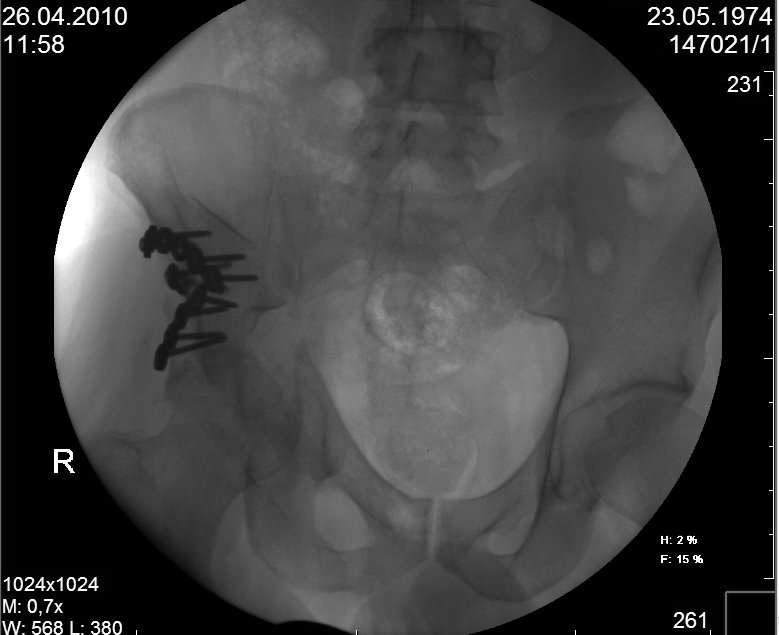

к таковым себя не причисляю, но...обычное дело для нашей страны - выкладывать 3D и не показывать стандартные проекции Judet. Дигност представляет те ракурсы, которые по-его мнению наиболее информативны, более того комп сам достраивает какие-то мелкие повреждения по 3D по своему усмотрению. По данной реконструкции можно предполагать высокий двухколонный перелом с оскольчатыми передней и задней колоннами, оскольчатую высокую переднюю колонну с задним полупоперечником или одно из перечисленных с вовлечение КПС. У меня впечатление за второй вариант, но нужно обследовать нормально - проекции, сканы.

высылаю дополнительно сканы.

Судя по представленным реконструкциям (не очень хорошего качества - много наводок)

мы имеем дело с полупоперечным переломом у которого отломался задний край или его отломали, превратив перелом в полный двухколонный.

По отдельным срезам и тем более по реконструкции трудно судить о сращении крыла и задней колонны с осевым скелетом.

Поэтому хотелось бы дообследовать больного (разумеется включив стандартные проеции judet,и срезы показывающие сращение)

Хорошо бы на рентгенограммы взглянуть и побольше срезов по своду. С каким отломком головка контактирует и как ее состояние.

Все выступающие коллеги высказались насчет необходимости стандартных снимков по Judet, потому что для определения тактики лечения переломов вертлужной впадины 3Д снимки малоинформативны.

Из того минимума, что представлено, мне кажется, мы имеем дело с двухколонным переломом вертлужной впадины. Обычно медиальный (центральный) "вывих" головки встречаются в сложных двухколонных переломах со смещением.